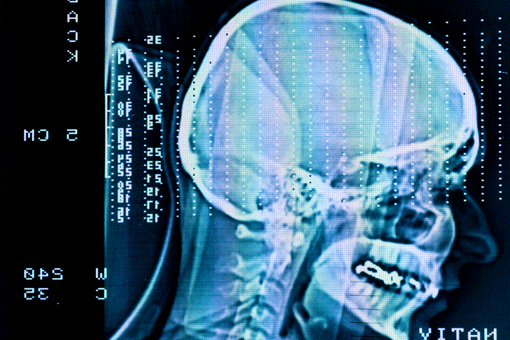

A GBM cobró la vida del ex Senador Edward Kennedy en 2009. La forma más agresiva de tumor cerebral primario, tumores de GBM suelen ser resistentes a las terapias estándar y la mediana de supervivencia es de aproximadamente tres a nueve meses para un tumor recurrente.

«Estamos hablando de tumores de crecimiento rápido que invaden el tejido normal del cerebro y son muy difíciles de tratar», dijo Orin Bloch, MD, neurocirujano en el Hospital Northwestern Memorial y el autor principal del estudio.» Estos tumores ocurren en hasta 23,000 estadounidenses cada año, y son típicamente tratados con resección quirúrgica del tumor seguida de quimioterapia y radioterapia.»